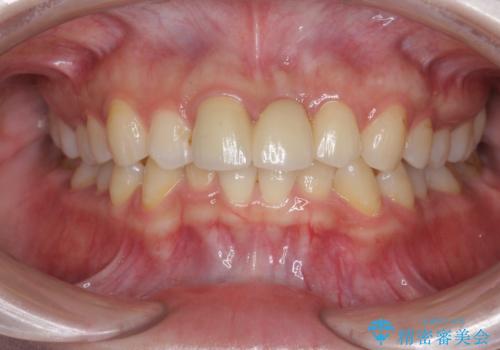

前歯のブリッジ治療

長期的な予後を見通すことが難しかったので、亀裂のある前歯の抜去を行いブリッジで審美性・機能性の回復を行いました。

- 36.3万円(仮歯・ジルコニアクラウン×3)費用は治療当時の料金となります